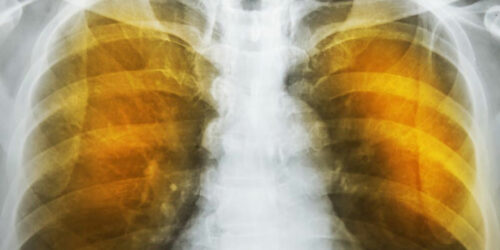

Emphysema is an oppressive respiratory disorder which results from the disintegration of the alveoli, i.e., the tissues where the interchange of gas with blood takes place. Destruction in any large scale will reduce the gas transfer area and the process of gas transfer itself, leading to oxygen starvation or hypoxia.